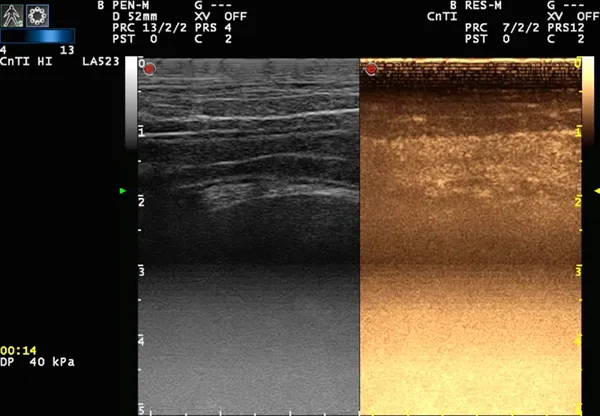

Contrast-enhanced ultrasound of the small intestine.

The first test used is a new type of ultrasound called contrast-enhanced ultrasound (CEUS). A harmless contrast medium consisting of microscopic bubbles is injected and allows the gut to “glow” for around 2 minutes, which enhances its features and gives an indication of blood flow to the tissue.